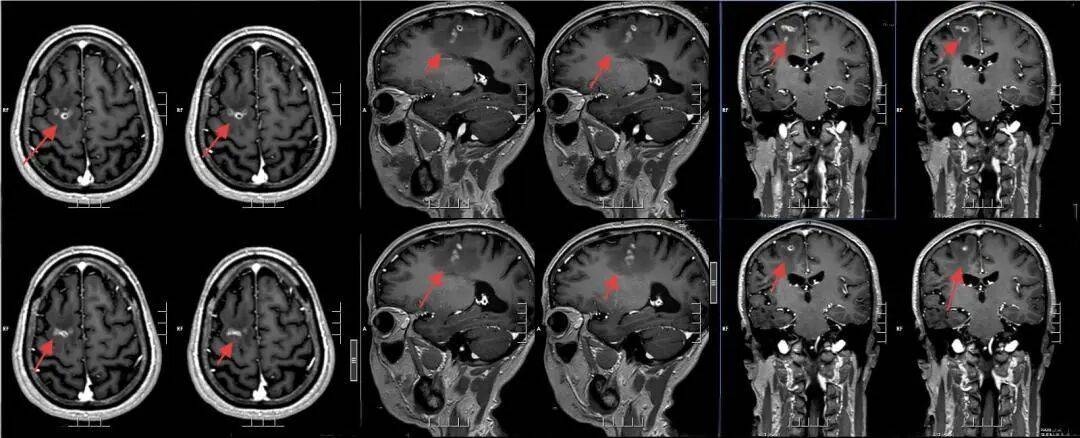

该院神经外二科张旭标副主任医师接诊后,根据影像结果,发现其右额叶病变,局部肉芽肿形成伴周围组织水肿怎么申请皇冠信用网 。“这是大脑为了隔离‘入侵者’筑起一道‘隔离墙’,周围的脑组织被刺激得肿胀。”张旭标解释,这些影像特征高度指向脑裂头蚴病。经比对,病灶范围稳定,手术时机成熟。

术前影像